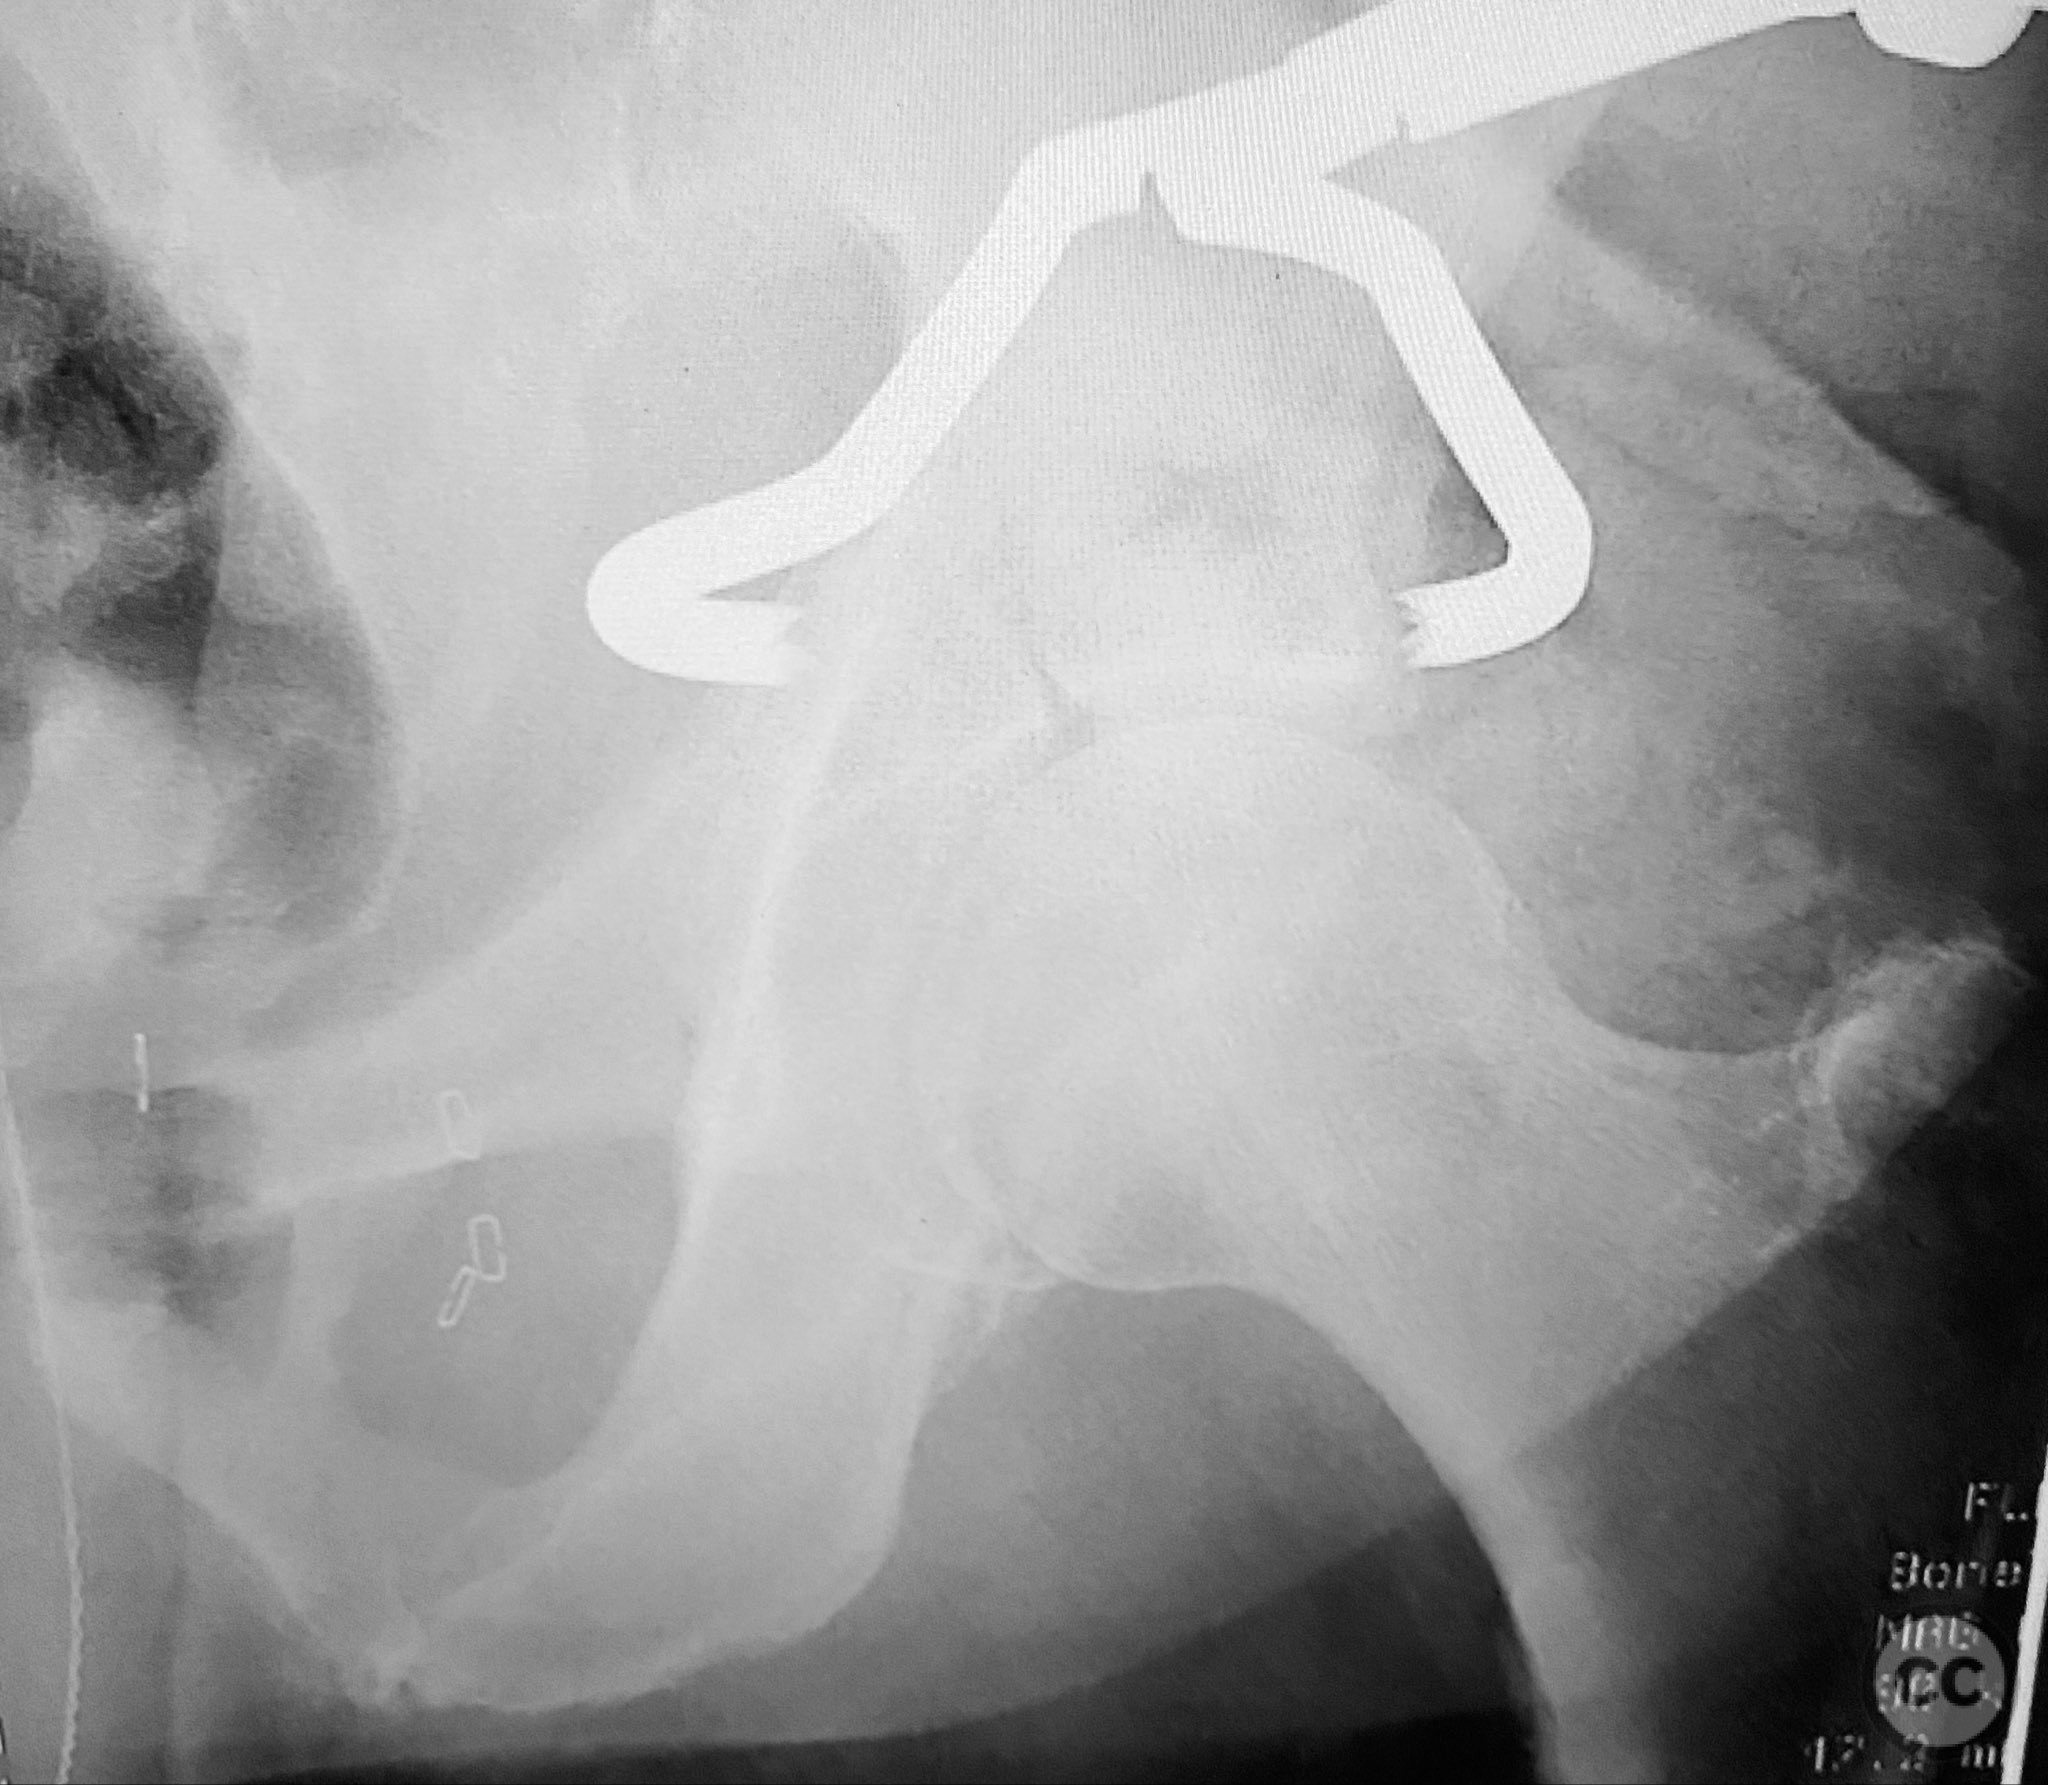

Clinical and radiological findings:  A 79-year-old male sustained a high-energy injury in a motor vehicle collision, resulting in a complex acetabular fracture-dislocation. Radiographs and computed tomography demonstrated a posterior wall and transverse acetabular fracture (AO/OTA 62-B1.3), with the posterior wall fragments displaying an atypical caudal hinge configuration. The medial wall fragment was non-articular. Axial imaging revealed an impacted osteochondral fragment obstructing reduction, as well as disruption of the capsular structures adjacent to the intact articular segment. The obturator internus tendon appeared taut but intact, with no evidence of sciatic nerve impingement or superior gluteal neurovascular compromise.

Planning remarks:  The preoperative plan included open reduction and internal fixation via a Kocher-Langenbeck approach in the prone position. The strategy entailed removal of the impacted intra-articular fragment, anatomic reduction and provisional fixation of the transverse component, reduction and fixation of the posterior wall, bone grafting and reduction of the impacted articular segment via the medial wall window, and definitive fixation of the medial wall. Capsular repair was planned prior to closure.

Anatomical surgical approach:  A standard Kocher-Langenbeck approach was performed, incising through the gluteal fascia and splitting the fibers of the gluteus maximus. The short external rotators were identified and protected, with subperiosteal dissection exposing the posterior column and wall of the acetabulum. The sciatic nerve was identified and mobilized laterally. The posterior capsule was found disrupted adjacent to the intact articular surface. The impacted osteochondral fragment was extracted from the joint space. The transverse fracture plane was debrided and reduced using clamps, with a greater trochanteric bone hook employed to manipulate the femoral head beneath the acetabular dome during reduction. Provisional fixation was achieved with a percutaneous lag screw across the transverse component. The peripheral posterior wall fragment was anatomically reduced and stabilized with a contoured plate. The medial wall defect provided access for reduction of the impacted articular segment, which was bone grafted prior to reduction and plating of the medial wall. Capsular tissues were repaired with nonabsorbable sutures prior to layered wound closure.

The posterior wall fragments exhibited an unusual caudal hinge morphology, necessitating careful mobilization to avoid propagation or comminution. Removal of the impacted intra-articular fragment was essential to achieve concentric reduction of the femoral head within the acetabular dome. Use of a greater trochanteric bone hook facilitated precise control of femoral head position during reduction maneuvers. The medial wall fragment, though non-articular, allowed direct visualization and accurate reduction of the impacted osteochondral segment, which was supported with bone graft prior to definitive fixation. Repair of disrupted capsular tissues was performed to restore soft tissue integrity and potentially reduce postoperative instability.